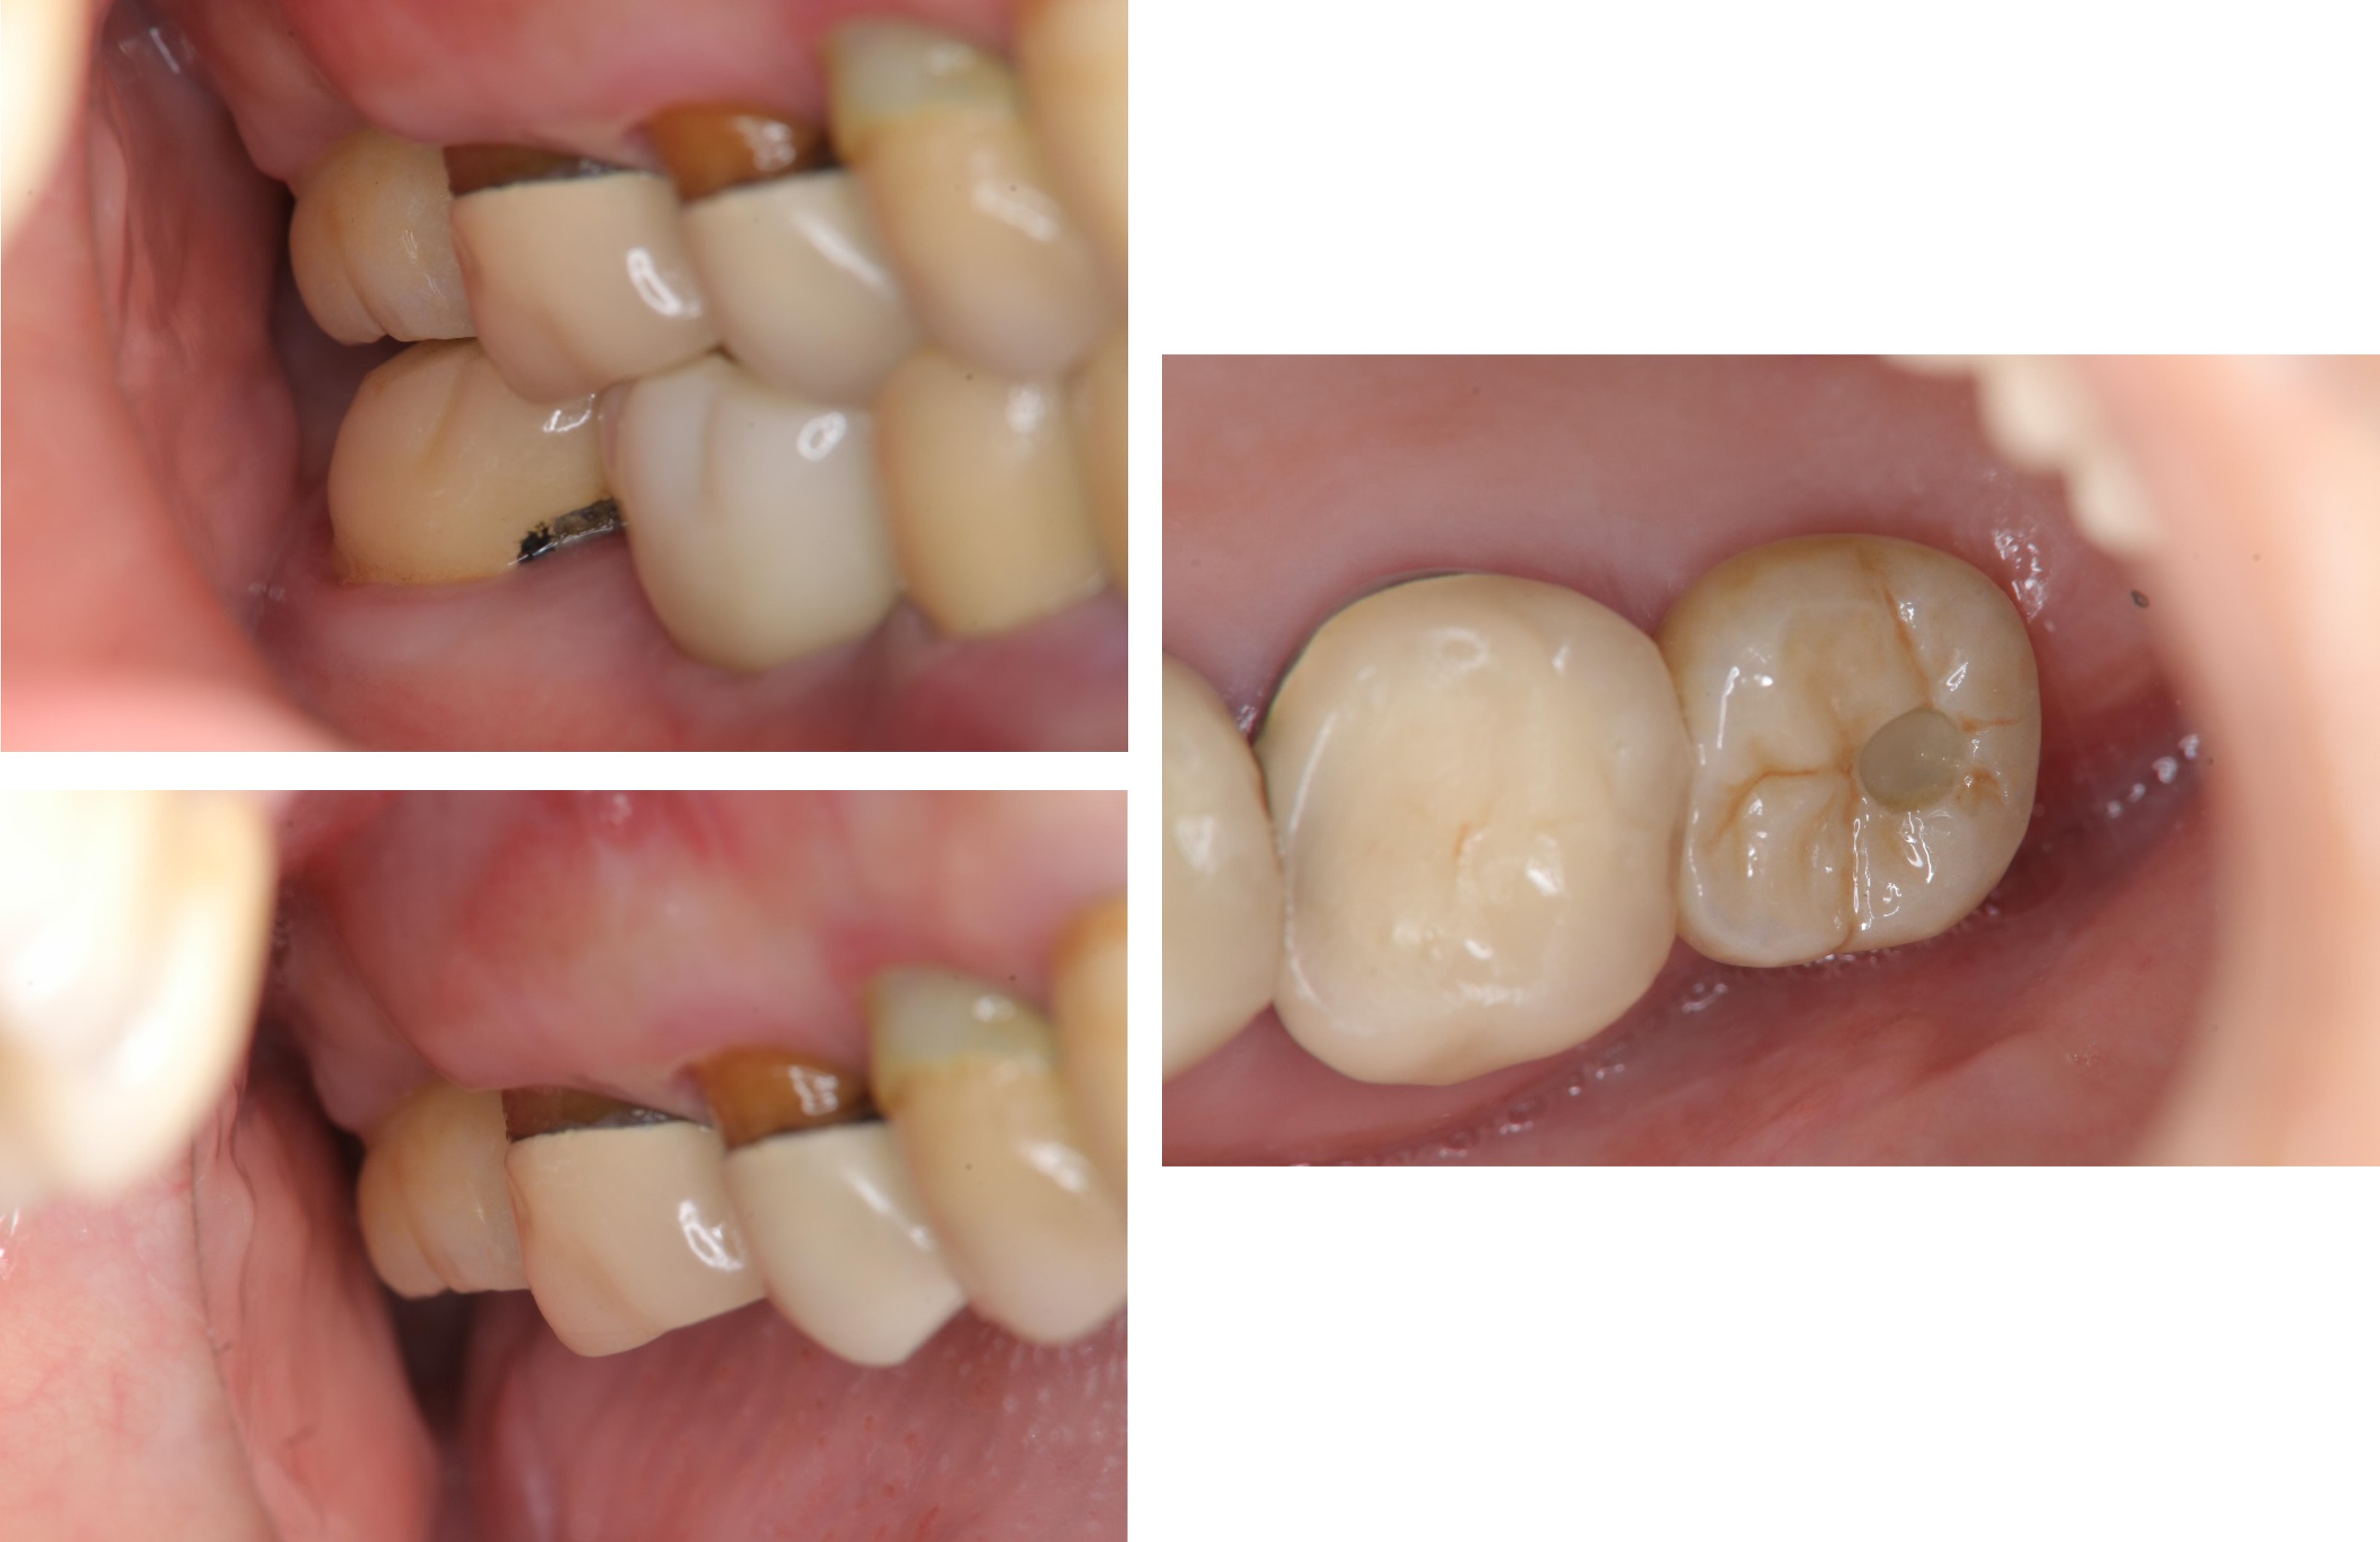

治療後,咬合牙周適應良好

治療後,密合度良好